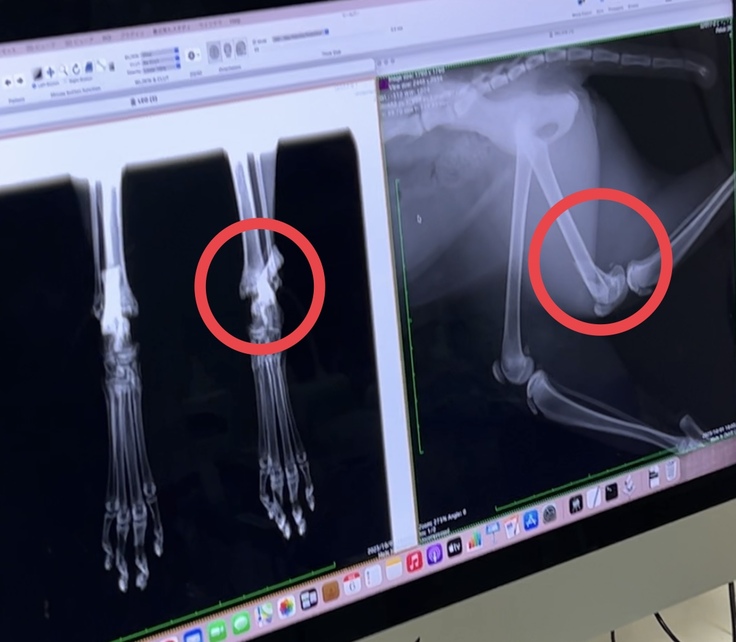

③10月2日 左脚2カ所の骨折発覚

順調に回復していたのですが、保護した日から立つ事も歩く事もないので、この日改めて脚のレントゲンを撮りました。

すると左脚に2箇所の骨折が判明しました。

▲左画:かかとの骨折 右画:膝上ももの骨折

膝上と踵の重要な箇所が折れていて子猫なこともありまだ成長するので、整形外科を得意とする腕のある医師に診てもらった上で、

設備の整った大きな病院での手術を勧められました。

▲術前検査の左大腿骨のレントゲン写真